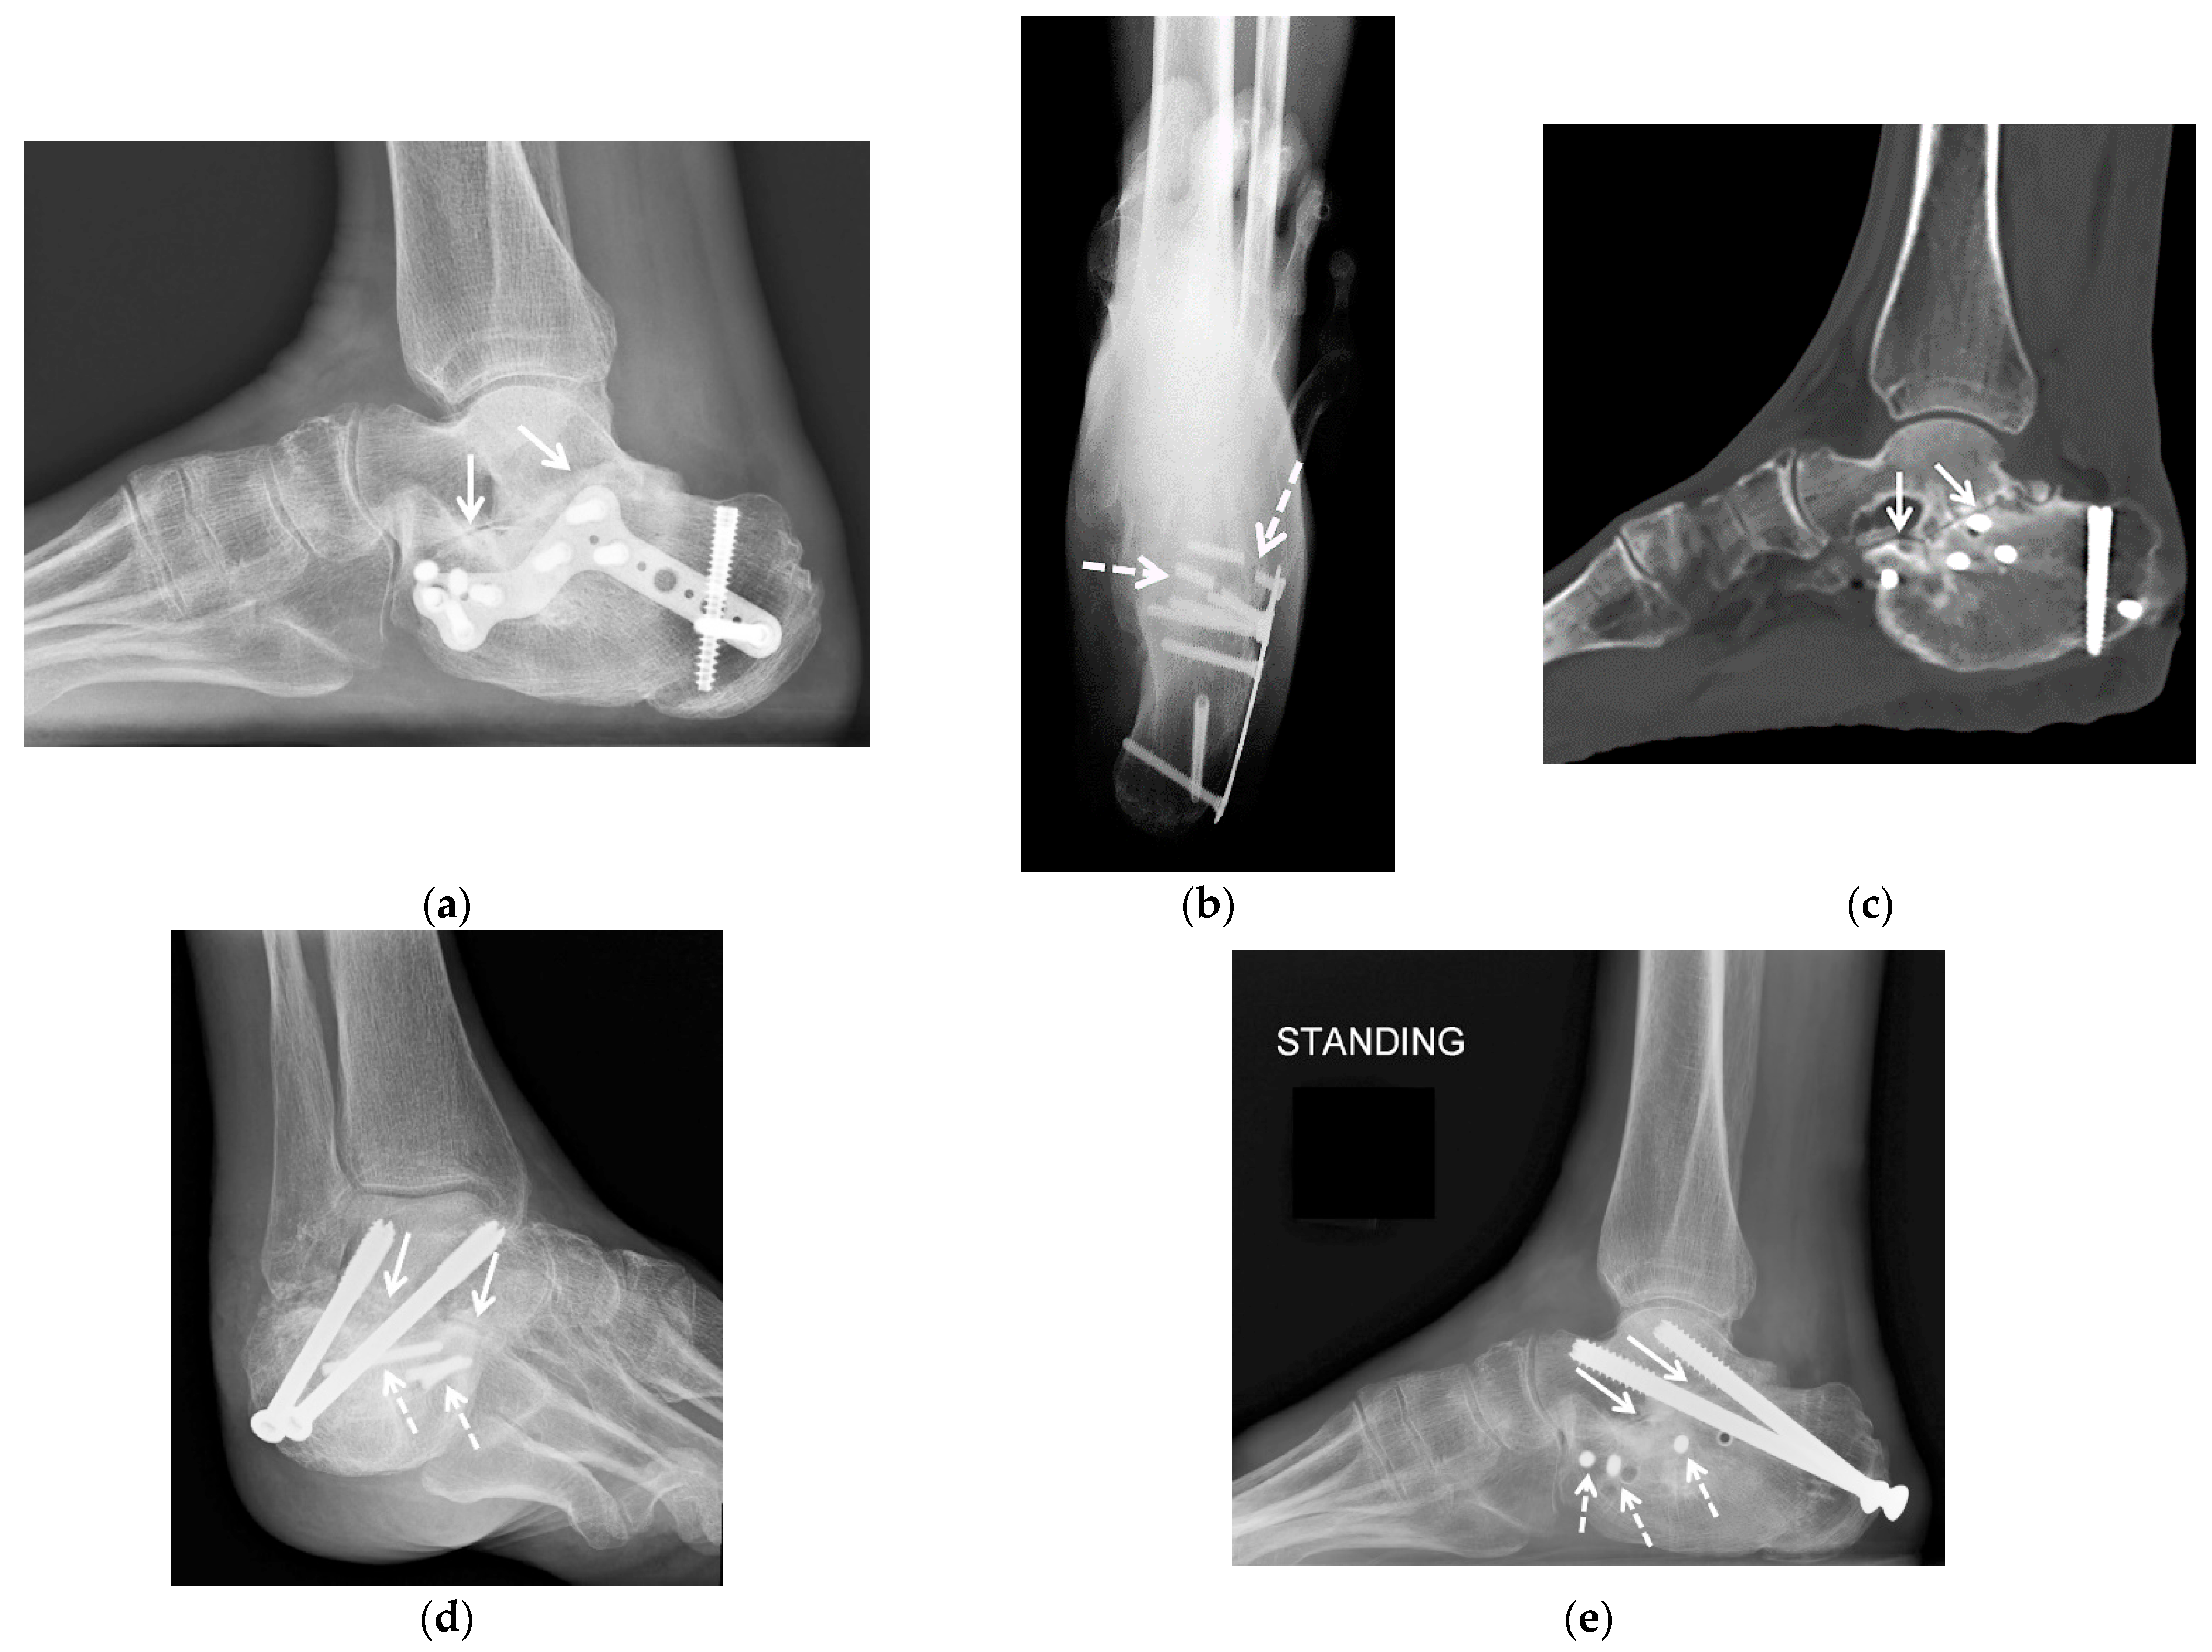

5.2.1. Joint-Preserving Procedures

5.2.2. Arthrodesis